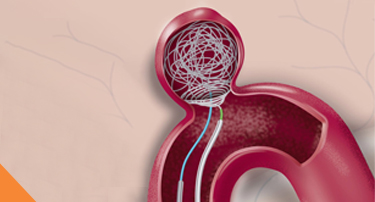

Aneurysm Coiling: How Modern Technology Prevents Brain Hemorrhage

A brain aneurysm (also known as a cerebral aneurysm or intracranial aneurysm) is like a bulge or ballooning in a blood vessel in the brain.

How AVM Embolisation Works: Procedure, Benefits, Risks, and Cost

The blood circulates through your body within an organized, closed circuit of blood vessels.